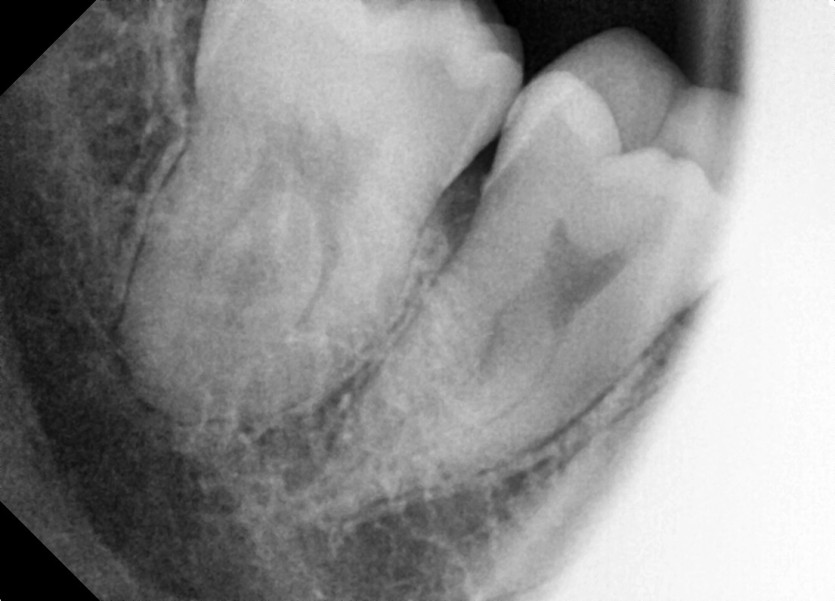

#18,28,38,48 사랑니 발치

구강 외과 전문의가 당일 발치했습니다.